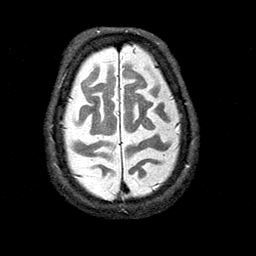

Alzheimer's disease MR T2-weighted -- Slice #40

Tour 1: Next/Previous/Start: This tour will examine the brain of an elderly woman with Alzheimer's disease. This brain displays many of the commonest features of the disease: brain shrinkage, or atrophy, and loss of function, as indicated by hypoperfusion (described in Tour 2). First, look at the prominent sulci, especially the central sulcus. Some reduction in brain volume is a part of normal aging, but compare this brain with the normal central sulcus, from a normal 81 year old woman. The abnormal shrinkage seen in this case, while not a finding specific to Alzheimer's disease, is severe and seems to affect some regions more than others.